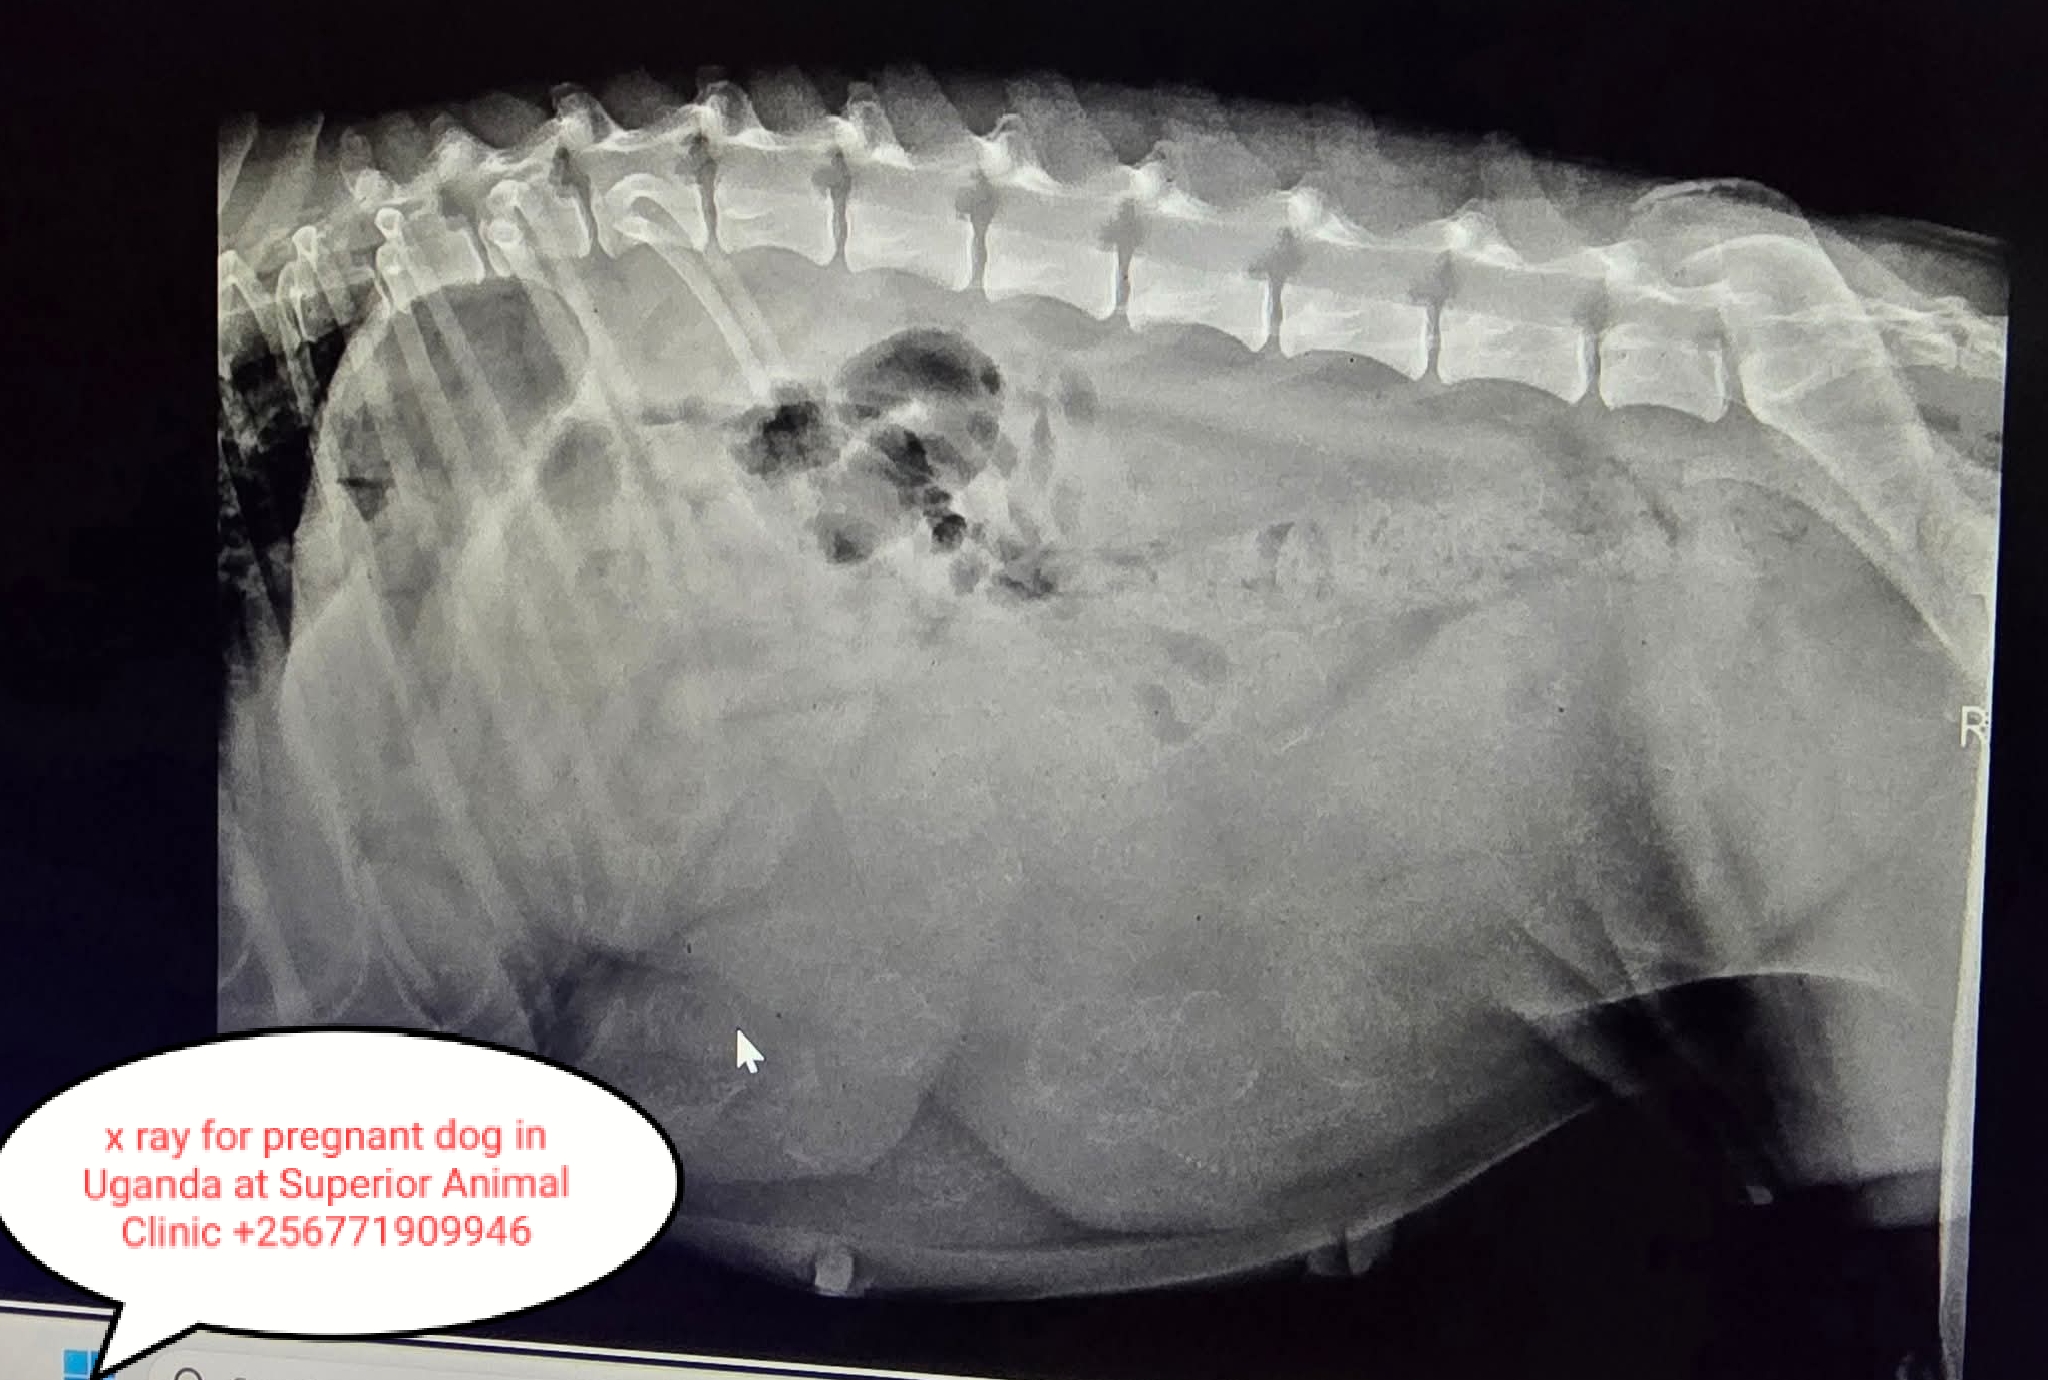

- Key weeks to watch: days 25–35 (ultrasound reliable), day 45+ (X-ray to count pups), final 2 weeks—rapid fetal growth and nesting.

- X-ray (radiograph): from day 45–55 to count pups and estimate size for whelping planning.

- One ultrasound at ~day 25–30, and one x-ray around day 45 if you need a count or suspect complications. More scans only if problems are suspected.